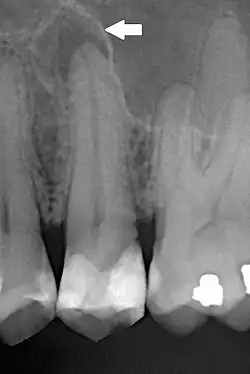

| Periapical dental radiograph showing chronic periapical periodontitis on the root of the left maxillary second premolar. Note large restoration present in the tooth, which will have undergone pulpal necrosis at some point before the development of this lesion. | |